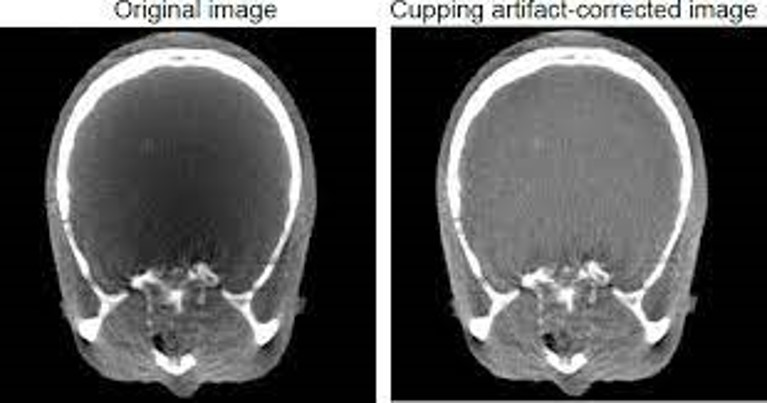

cupping artifact on left, post correct on right.

X rays passing through the middle portion of a uniform cylindrical phantom are hardened more than those passing though the edges because they are passing though more material. As the beam becomes harder, the rate at which it is attenuated decreases, so the beam is more intense when it reaches the detectors than would be expected if it had not been hardened. Therefore, the resultant attenuation profile differs from the ideal profile that would be obtained without beam hardening (Fig 2). A profile of the CT numbers across the phantom displays a characteristic cupped shape